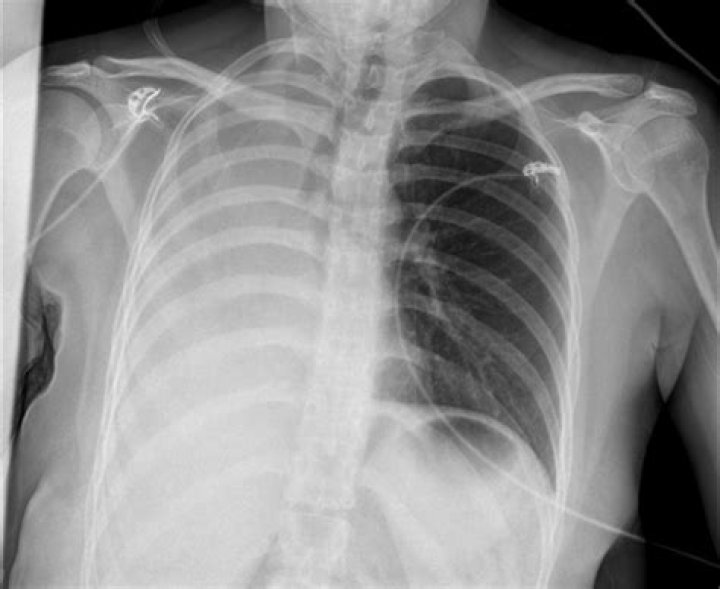

Pneumothorax is the most common complication of transthoracic lung biopsy (4). A patient with stable pneumothorax may be treated conservatively without chest tube insertion. If pneumothorax is large (greater than 30% of hemithorax), is rapidly expanding, or is causing symptoms, chest tube insertion is warranted.

Most studies report a 20% to 25% incidence of pneumothorax after TTNB of the lung, with higher rates when patients have moderate-to-severe emphysema or with core biopsy.

Pneumothorax. The most common complication of chest biopsy is development of a pneumothorax. The largest retrospective series placed the incidence of pneumothorax at 20.5% and the incidence of pneumothorax requiring chest drainage at 3.1%.

What happens when one lung collapses?

A collapsed lung occurs when air escapes from the lung. The air then fills the space outside of the lung between the lung and chest wall. This buildup of air puts pressure on the lung, so it cannot expand as much as it normally does when you take a breath. The medical name of this condition is pneumothorax.